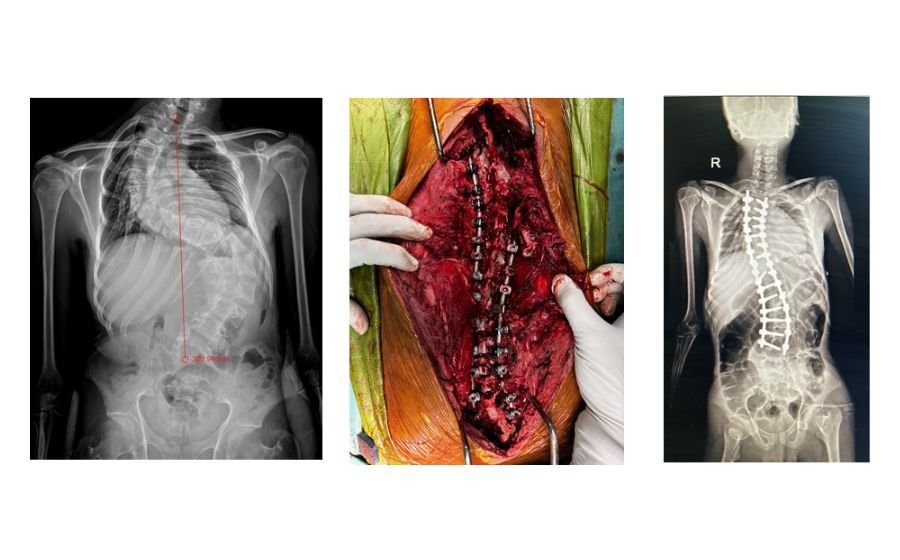

Scoliosis Surgery

Scoliosis surgery is performed when a spinal curve becomes severe enough to affect posture, balance, breathing, or overall comfort. The procedure straightens and stabilizes the spine using screws and rods, allowing the bones to fuse in a corrected position. Throughout the surgery, advanced neuromonitoring is used to continuously check the function of the nerves and spinal cord, adding an extra layer of safety and ensuring precise, protected correction. The goal is to restore alignment, prevent curve progression, and help patients stand straighter and return confidently to daily life.